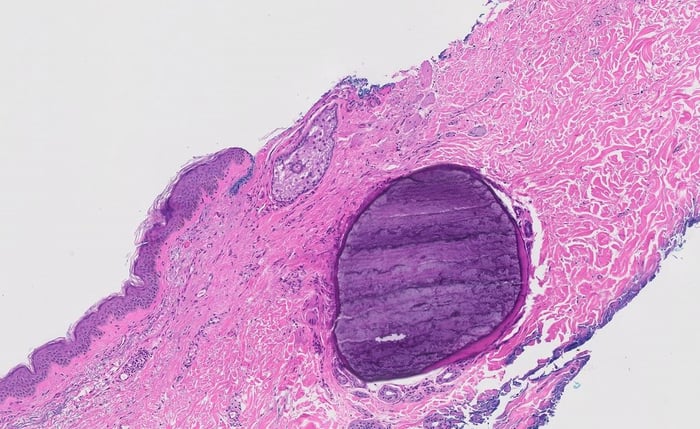

Histopathology images:

This lesion actually turned out to be metaplastic bone, a benign mimic of melanoma.